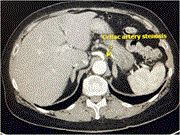

Unique multidisciplinary approach in a patient with small bowel obstruction and chronic mesenteric ischemia

Sally Tan and others

Journal of Surgical Case Reports, Volume 2023, Issue 10, October 2023, rjad577, https://doi.org/10.1093/jscr/rjad577